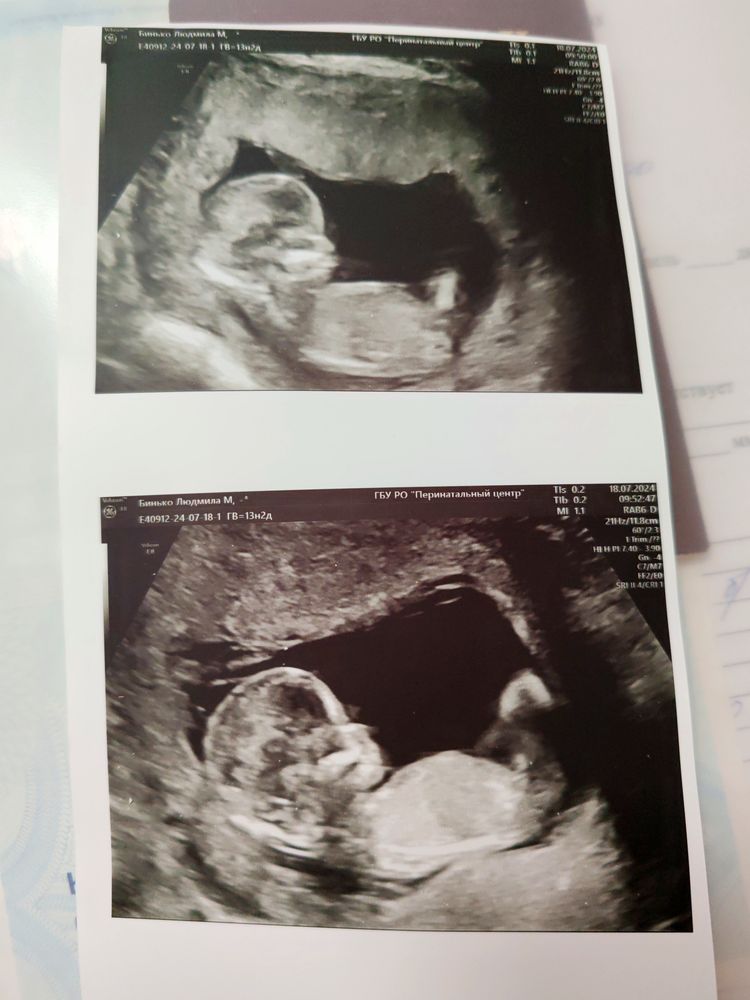

Была на узи в 12 недель, врач сказал, что предположительно девочка. Сегодня так получилось, что в 13 недель ещё раз попала на узи. И пока смотрели животик малыша, был вид снизу, фото нет, но там точно виднелось что-то не девчачье)) ЧСС 170, но у меня и мальчиков и у девочки так на первом скрининге.

Людмила Дизайн интерьера, я сбоку ничего понять не могу, мне показывали со стороны попы что ли

Анютик, со стороны попы я и разглядела, как что-то торчит)) Хотя на этом сроке может у обоих полов торчать, все же очень было похоже на мужские органы) мне и по внешнему виду уже сказали девочки, что точно парень)